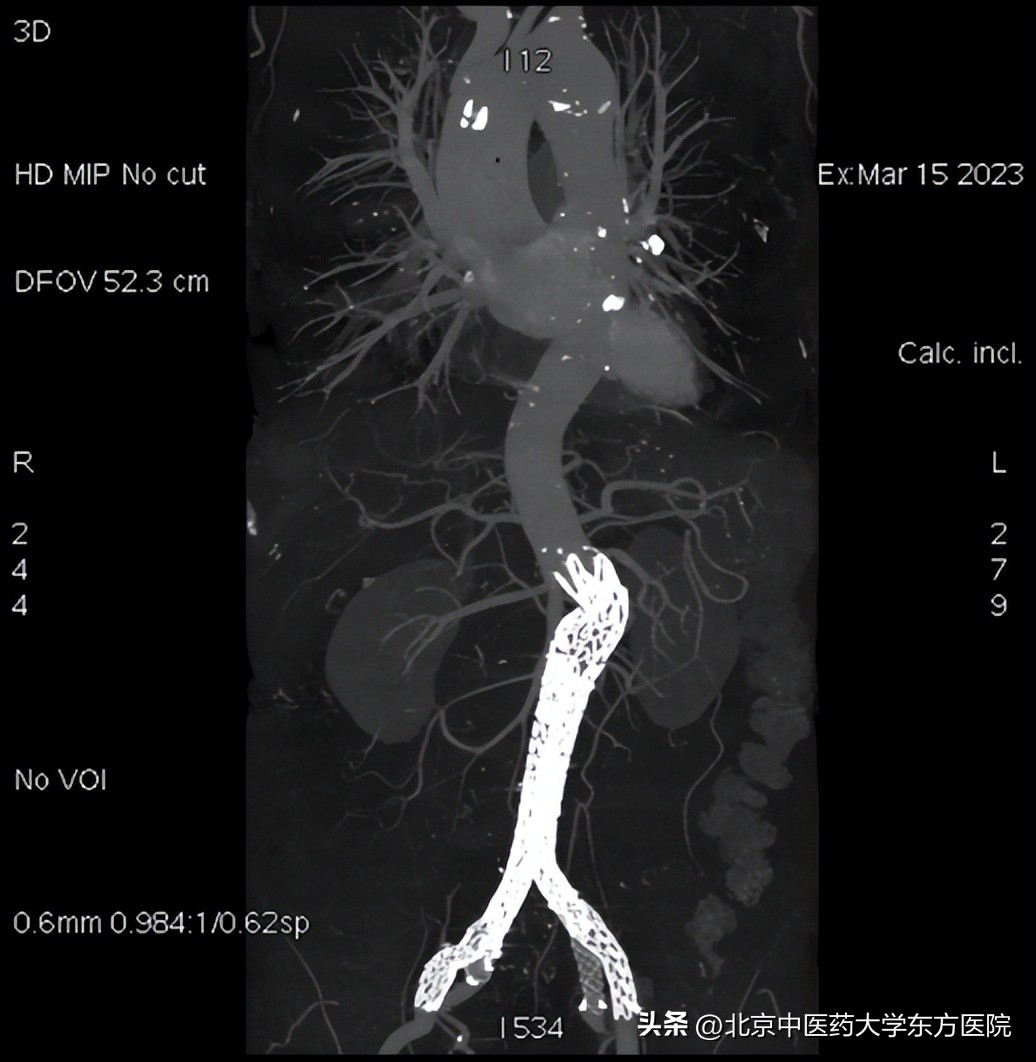

入院后外四科团队在对病例进行全面分析、充分讨论,患者年龄相对较轻,结合其盆腔供血情况,为达到更佳疗效,避免并发症的发生,故决定在“拆除腹腔定时*弹炸**”的同时,重建双侧髂内动脉的手术方式,不放弃任何一条血管,力争完美解决腹主动脉和髂动脉血管瘤体问题,并且对患者的正常功能最大程度的保留。经过术前模拟等周密准备,由科室杨宝钟主任指导,顾汉程、黄强、曹刚、李光宗医生上台,在麻醉科、导管室、放射科以及护理同仁的通力配合下,团队历时5个半小时顺利完成该手术。术后复查支架放置精准,血流通畅,血管形态完美,无各型内漏。患者无不适症状,术后第二天正常下地活动,目前已康复出院。

(术后)

(术前术后对比图)